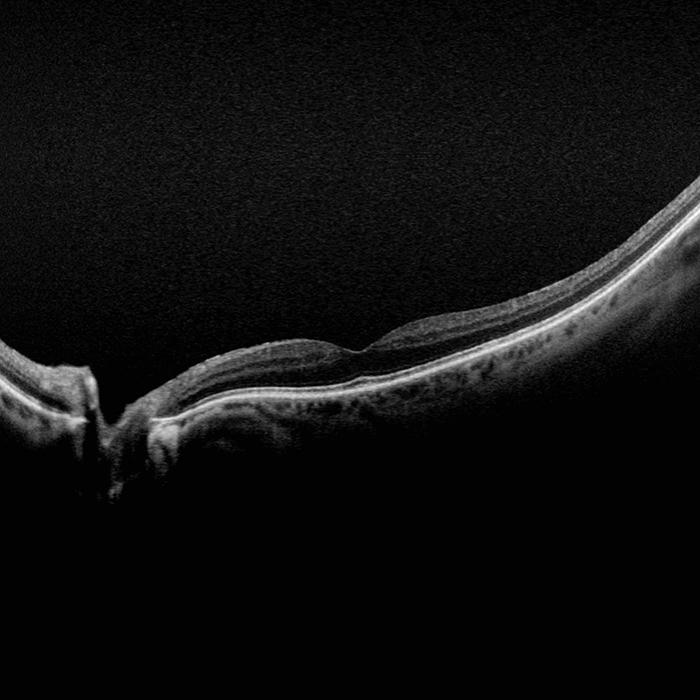

Silverstone RGB is redefining excellence in retinal imaging. It is the only device that captures true color, 200° optomap ultra-widefield images in a single shot, seamlessly integrated with guided swept-source OCT. For the first time, eye care professionals can access nine powerful imaging modalities in one system, each designed to image pathology anywhere in the retina.

optomap has been shown to enhance pathology detection, disease management, and to improve clinic flow. Now with nine retinal imaging modalities, including integrated, peripheral Swept Source OCT, Silverstone RGB facilitates examination of the retina from vitreous through the choroidal-scleral interface.

Silverstone RGB imaging modalities and image viewing options:

- SS-OCT

- OCT: Up to 23mm line scan and swept-source functionality